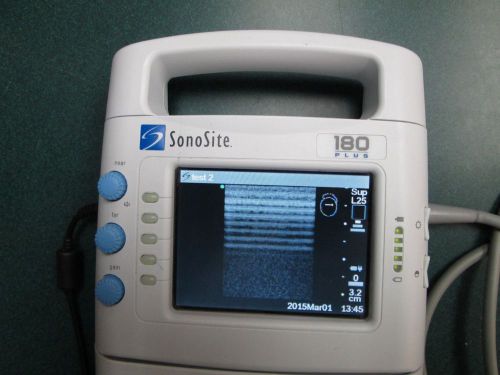

US $4400

| “This probe is in good operational condition with a few weak elements on the image.” |

| Serial Number | 30340 |

Sonosite 180 plus ultrasound and L25 linear probe transducer